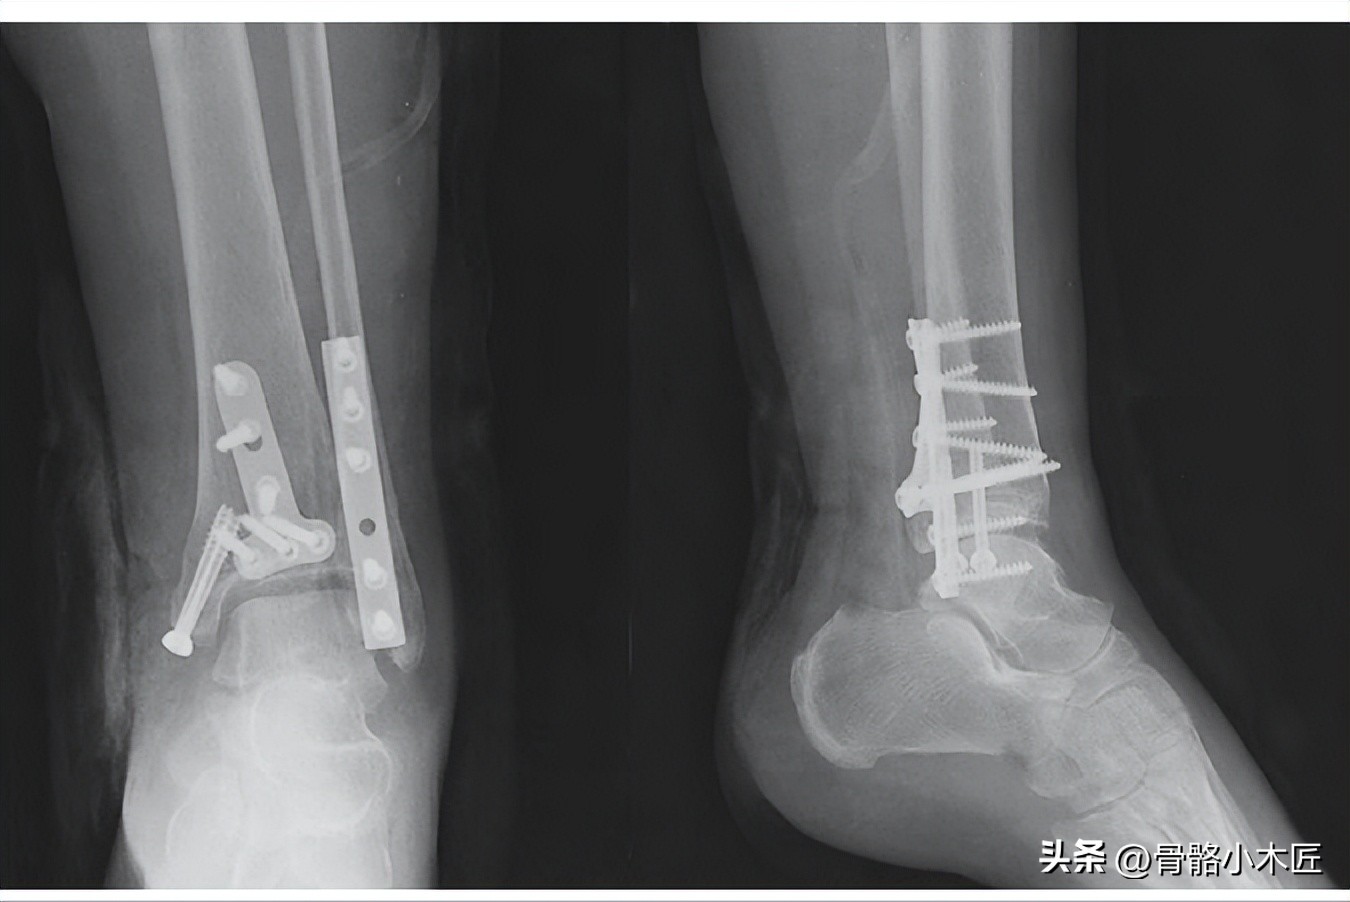

有移位的骨折往往因为导致附着的韧带松弛,手法复位难以成功,即使复位成功也难以维持韧带张力,应切开复位。大多数的踝部骨折需要行手术治疗,伴随其他损伤,还需要修复韧带,修复关节囊等,伴随关节面压缩等可能还需要通过植骨等填充。

骨折固定图片

固定稳定情况下,术后可早期进行无负重功能锻炼,预防关节僵硬,10-12周左右骨折确定愈合后开始逐渐负重行走;如骨折粉碎,固定相对不稳定时,术后可能还需要配合石膏等外固定进行早期制动,4-6周左右根据愈合情况拆除石膏进行关节的功能锻炼。